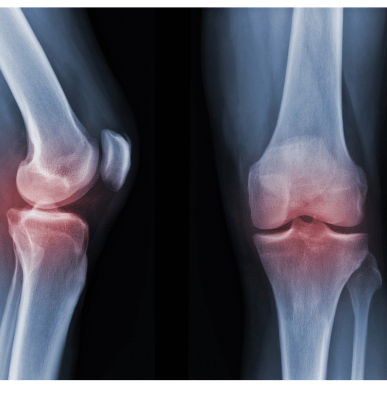

Rheumatological issues refer to a wide range of diseases affecting the joints, muscles, and connective tissues. These conditions are typically autoimmune or inflammatory in nature, where the immune system mistakenly attacks the body’s tissues. Common rheumatological disorders include rheumatoid arthritis, lupus, gout, and ankylosing spondylitis. These issues can cause chronic pain, stiffness, swelling, and loss of function in the affected areas.

The symptoms of rheumatological issues vary but commonly include joint pain, swelling, and stiffness, particularly in the morning or after periods of inactivity. Fatigue, muscle weakness, and fever are also common. In conditions like rheumatoid arthritis, joints may become deformed over time. Lupus, another rheumatological disease, can cause skin rashes, kidney problems, and heart complications.

Arthritis is a common yet complex condition that affects millions of people worldwide. Finding an arthritis doctor in my area who understands the nuances of this disease is crucial for effective treatment and management. At Health Sphere: Dr. Borse’s Multispeciality clinic Ravet, our arthritis specialists are experienced in diagnosing and treating various forms of arthritis, including osteoarthritis, rheumatoid arthritis, psoriatic arthritis and many more.